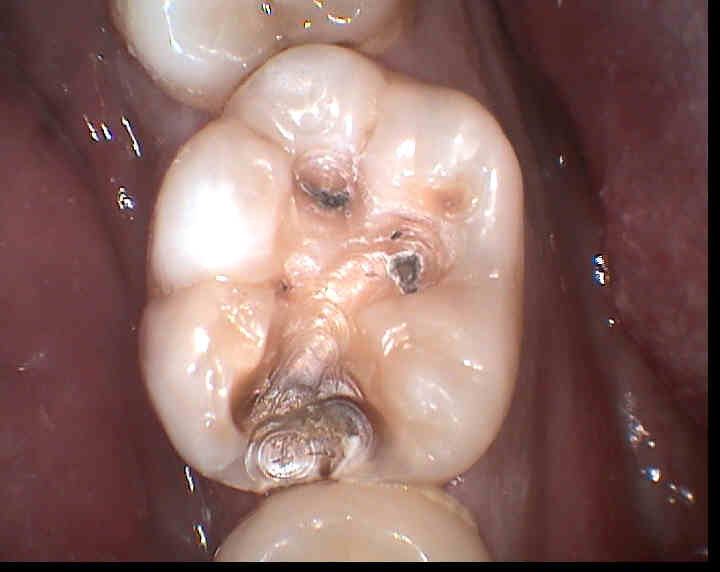

1-1 虫歯などで神経の近くまで治療した場合 悪化した虫歯は、深い部分まで削ることがあります。

【原因】 虫歯の治療では、歯を削る際の熱や振動、麻酔、詰め物をするときの乾燥などによって神経が刺激されます。

5すでに歯の神経が炎症を起こしていた場合 痛みやしみる症状を数カ月に渡って繰り返していた場合や、神経ギリギリの深さの虫歯などは、虫歯で溶かされた歯を綺麗に取り除いても、神経内部に入り込んだ虫歯菌までは取り除くことができないため、治療後に痛くなることがあります。